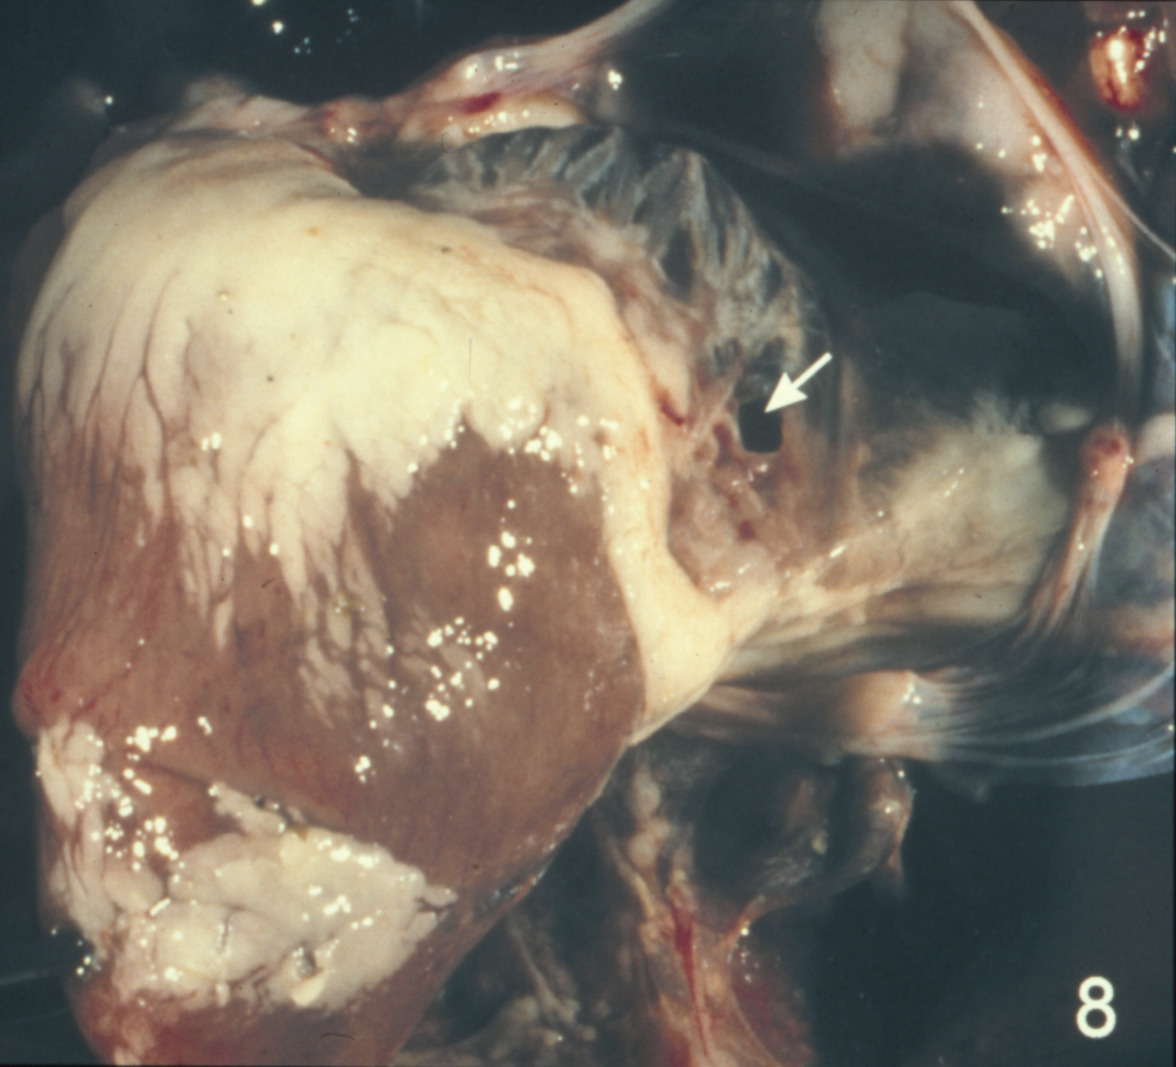

Cardiovascular disease in turkeys (slide study set no. 24)

Turkeys--Diseases Cardiovascular system--Diseases

Slide Study Set #24, Cardiovascular Diseases in Turkeys (includes 27 color slides), 2001